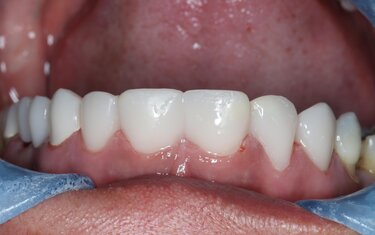

Figure 11: The patient was asked to wear the temporaries for a week to assure fit, function and esthetics of the treatment proposal.